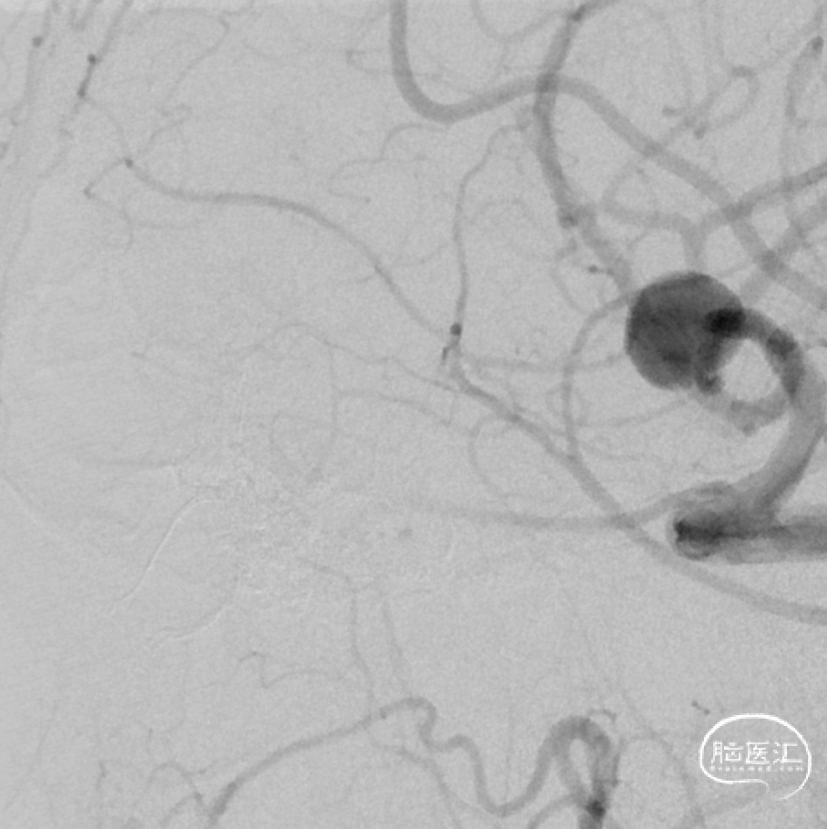

治疗经过

二期治疗